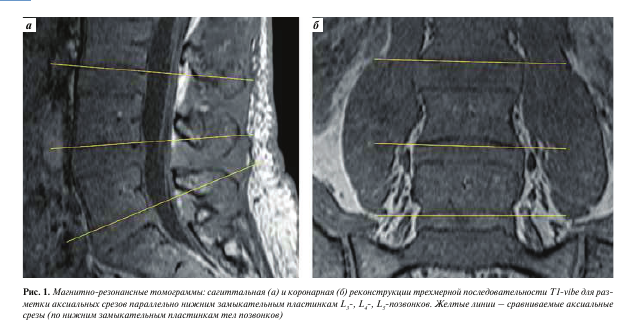

Изображения, полученные с помощью вышеописанной последовательности T1-vibe без жироподавления, открывали в программе InobitecPro в режиме мультипланарной реконструкции, где строились аксиальные срезы, параллельные в коронарной и сагиттальной проекциях нижним замыкательным пластинкам L3-, L4-, Ь5-позвонков (рис. 1). На построенных изображениях на всех 3 уровнях с помощью инструмента «ROI полигон» обводили многораздельные мышцы с обеих сторон, как показано на рис. 2 (вдоль границы остистого и суставного отростков, затем по фасции многораздельной мышцы), для оценки средней интенсивности сигнала и площади выделенной зоны. Кроме того, в режиме T1-vibe без жироподавления с помощью инструмента «ROI овал» измеряли среднюю интенсивность сигнала в жировой клетчатке слева от паравертебральных мышц (см. рис. 2).

Описанные нами при визуальном анализе МРТ- изображений анатомические особенности прикрепления и расположения паравертебральных мышц подтверждают данные, ранее опубликованные как анатомами [9], так и нейрохирургами [14]. Кроме того, очевидно, что угол наклона среза важен для объективизации оценки структуры мышцы. Безусловно, наиболее удобным является позиционирование среза для оценки параллельно замыкательным пластинкам позвонков, что обеспечит наиболее перпендикулярный срез мышцы, а также в определенной степени нивелирует индивидуальные различия между пациентами в связи с разнонаправленными дегенеративными изменениями. По данным нашего исследования, наиболее удобна оценка жирового замещения на уровне, параллельном нижней замыкательной пластинке Ь4-позвонка, что обусловлено определенным расположением анатомических ориентиров (остистого отростка, мест прикрепления фасций мышц) на этом уровне. Разные исследовательские группы публиковали работы как с качественной оценкой жировой инволюции мышц [4,15], так и с количественными методами оценки. Как отмечено выше, качественная оценка в высокой степени субъективна, зависит от опыта врача и вследствие этого малонадежна и маловоспроизводима. Представленные ранее количественные методы оценки паравертебральных мышц, безусловно, объективны, однако сложны для рутинного использования, так как требуют дополнительного программного обеспечения и более длительны по времени [8]. Оптимальным для количественной оценки жирового замещения является расчет фракции жира с помощью данных изометрической последовательности T1-vibe с методикой жироподавления Dixon, однако она достаточно длительна и доступна не на всех сканерах [11]. Предложенный нами индекс жирового замещения прост в использовании, калькуляция его возможна на любой аксиально-ориентированной последовательности с Т1-контрастностью без жироподавления, в том числе неизометрической, при условии правильного позиционирования срезов — параллельно нижней замыкатель- ной пластинке Ь4-позвонка на сагиттальных и коронарных изображениях, так как, по нашим данным, именно на этом уровне наблюдался наименьший разброс показателей индекса жирового замещения. С учетом высокого коэффициента корреляции индекса жирового замещения с фракцией жира, которая является более точным, но менее доступным показателем, мы считаем предложенный индекс перспективным показателем для оценки состояния мышц.